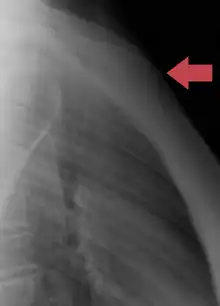

Sternum seen posteriorly

Sternum, lateral aspect